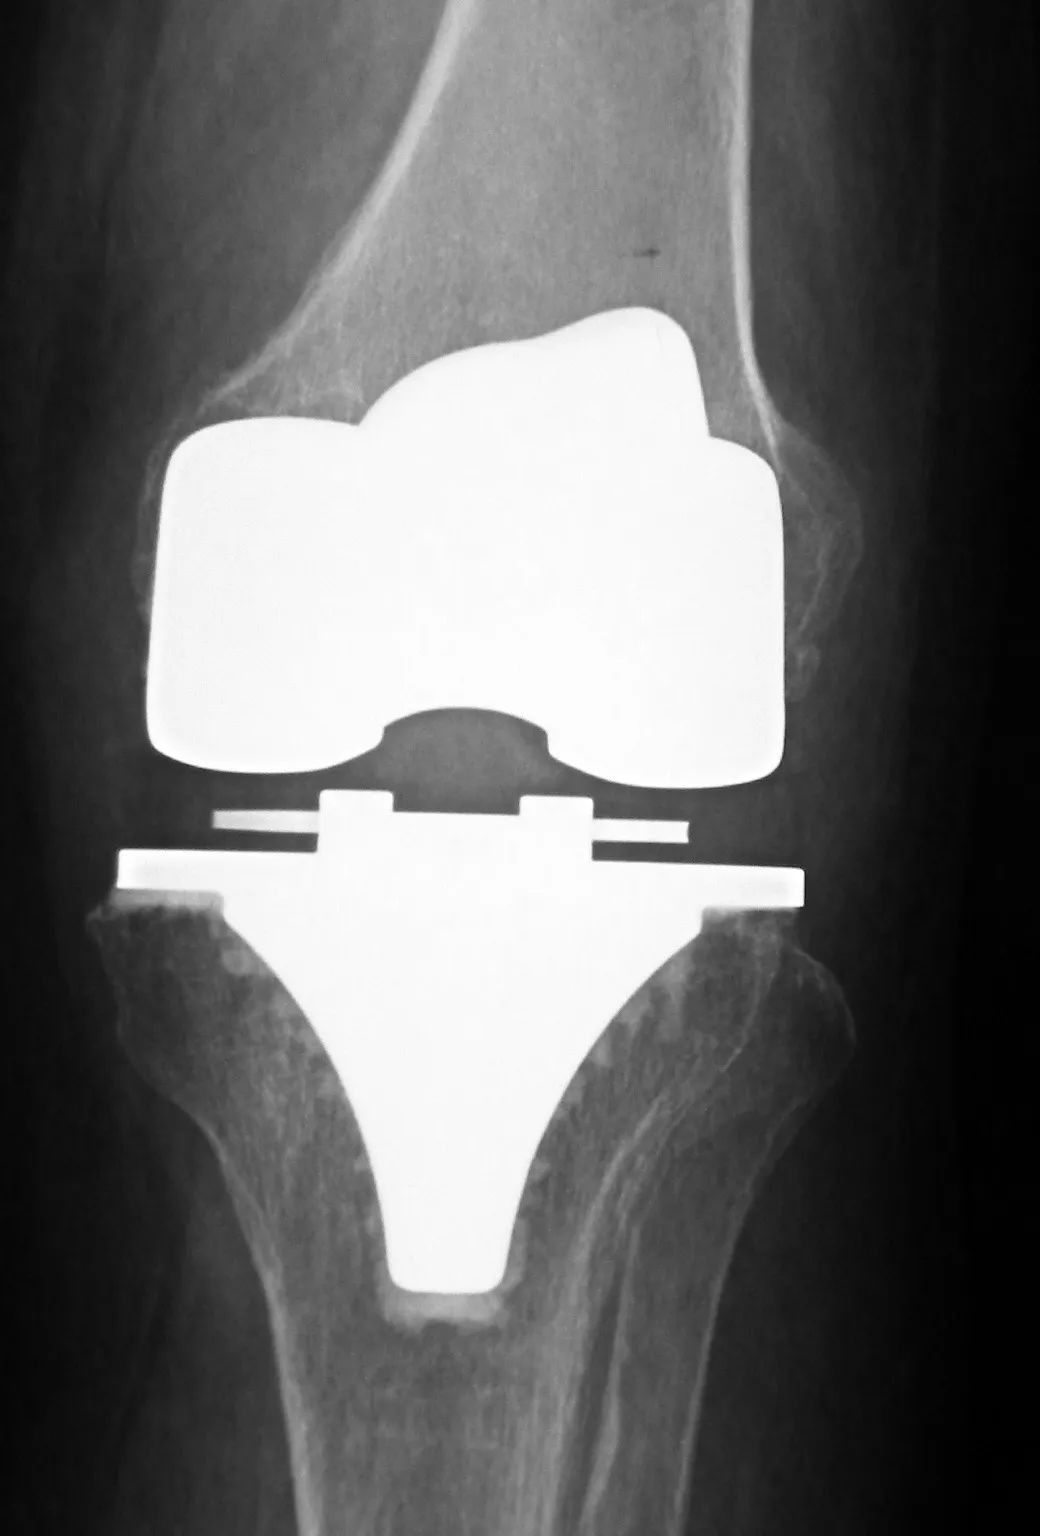

人工髋、膝关节置换是治疗各种原因导致的关节终末期疾病的最有效方法,已经在世界范围内广泛开展。目前,我国人工关节事业进入快速发展阶段,据统计,截至2019年,全国髋、膝关节置换年手术量逾90万台,国产假体构成比例逐年上升。